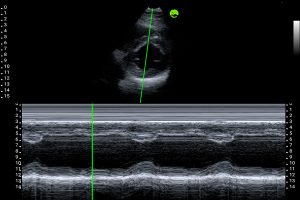

Trained on millions Cardiac & OBGyn Ultrasound Images

Built from a dataset of millions de-identified ultrasound images, our AI models cover Obstetrics, Cardiology, and Gynecology. They analyze key anatomical structures in real time, providing accurate biometric measurements and insights that help clinicians assess fetal growth, cardiac function, and organ health with greater speed and confidence.

AI Powered Acquisition

- Real-time guidance during scanning

- Automatic quality assessment

- Reduced operator variability

- Faster scan completion